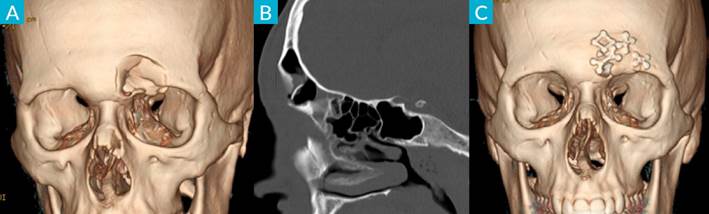

There are many classifications of zygomatic fractures, most are described on CT findings (Fig. 2).